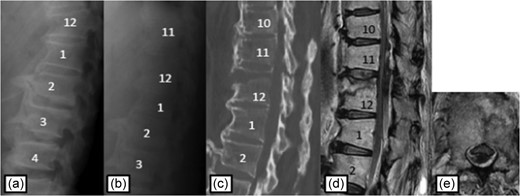

Plain radiographs on initial assessment (a) and on admission (b); Sagittal CT image (c) showing the hyperextension fracture at L1 and dislocation of it; MRI T2-weighted image (d, e) showing the severely compressed spinal cord at T12 level.